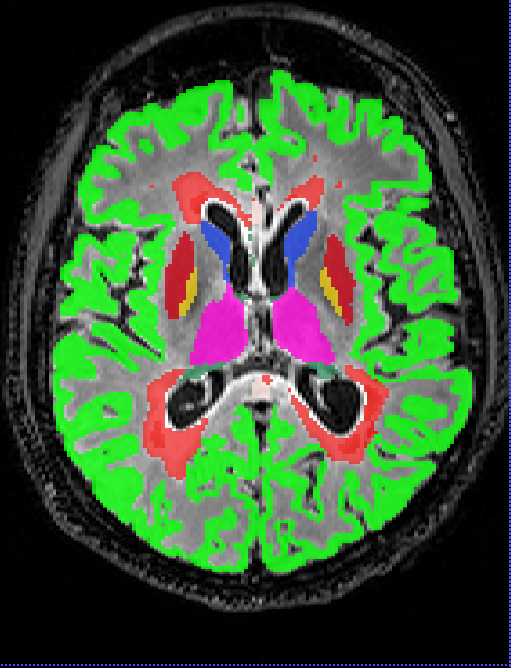

Performance metrics on the Insel32 dataset (vs the consensus segmentation) are summarised in Table 2, along with inter-rater comparison between the two raters, and between the raters and the consensus. An example of output of the methods considered, together with the manual ground truth, can be seen in Figure 2.

Box plots of the Dice coefficient for the segmentation (DeepSCAN multi-task) of various grey matter structures, when compared with Freesurfer, can be found in Figure 3. Both models performed quite robustly when applied to the Insel32 dataset. However, the nnUnet model can be seen to make substantial errors in the placing of structures on the MSSEG (out of sample) dataset, as can be seen in Figure 4.